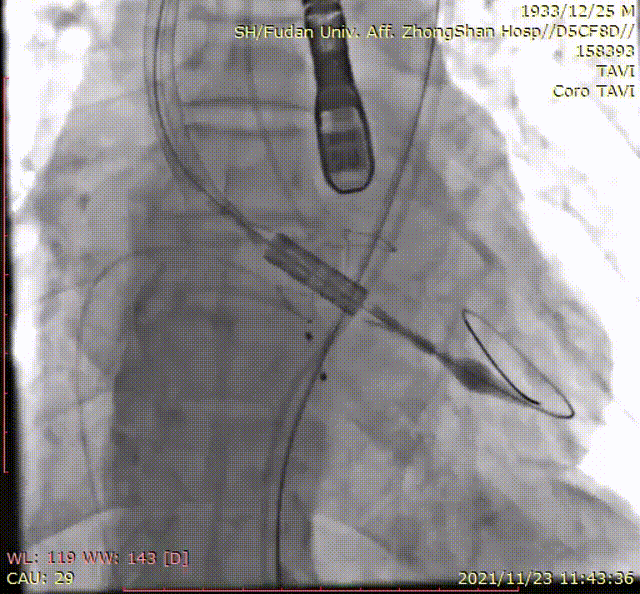

输送系统到位

定位环释放